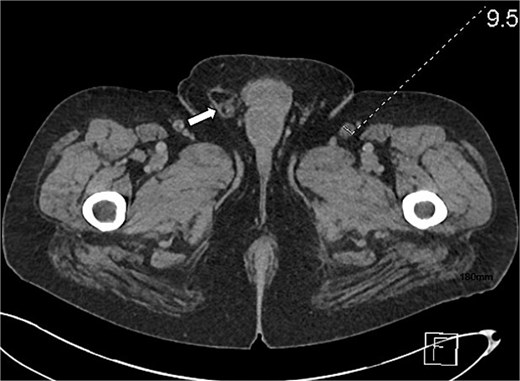

CTAP showed focal inflammatory fat stranding and minor un-encapsulated fluid around and between the second and proximal third parts of the duodenum, with an eccentrically thickened medial wall. The inflammation extended to involve the head and uncinate process of the pancreas (Figs 3 and 4). Acute groove-type pancreatitis is the favored diagnosis given the elevated amylase levels. However, acute duodenitis remains a differential diagnosis. Additionally, mural fat in the caecum and ascending colon was observed, consistent with chronic Crohn’s disease (Fig. 4), and a right-sided fat-containing inguinal hernia was also noted (Fig. 5).

Axial section of abdominal CT scan. The axial section of the abdominal CT scan shows a right sided fat containing inguinal hernia.